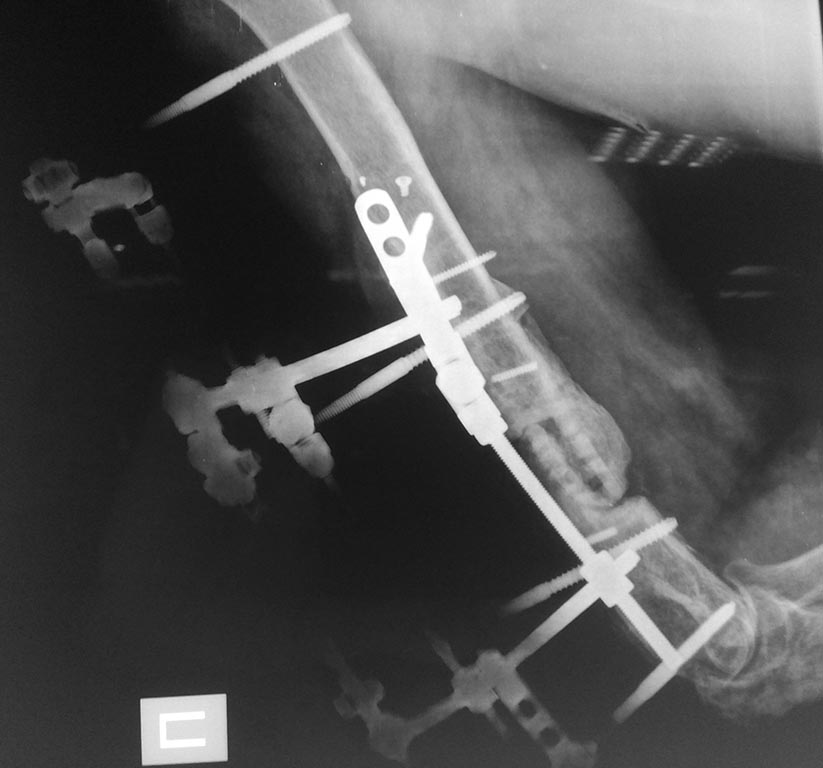

5 месяцев с АВФ

5 месяцев с АВФ боковая